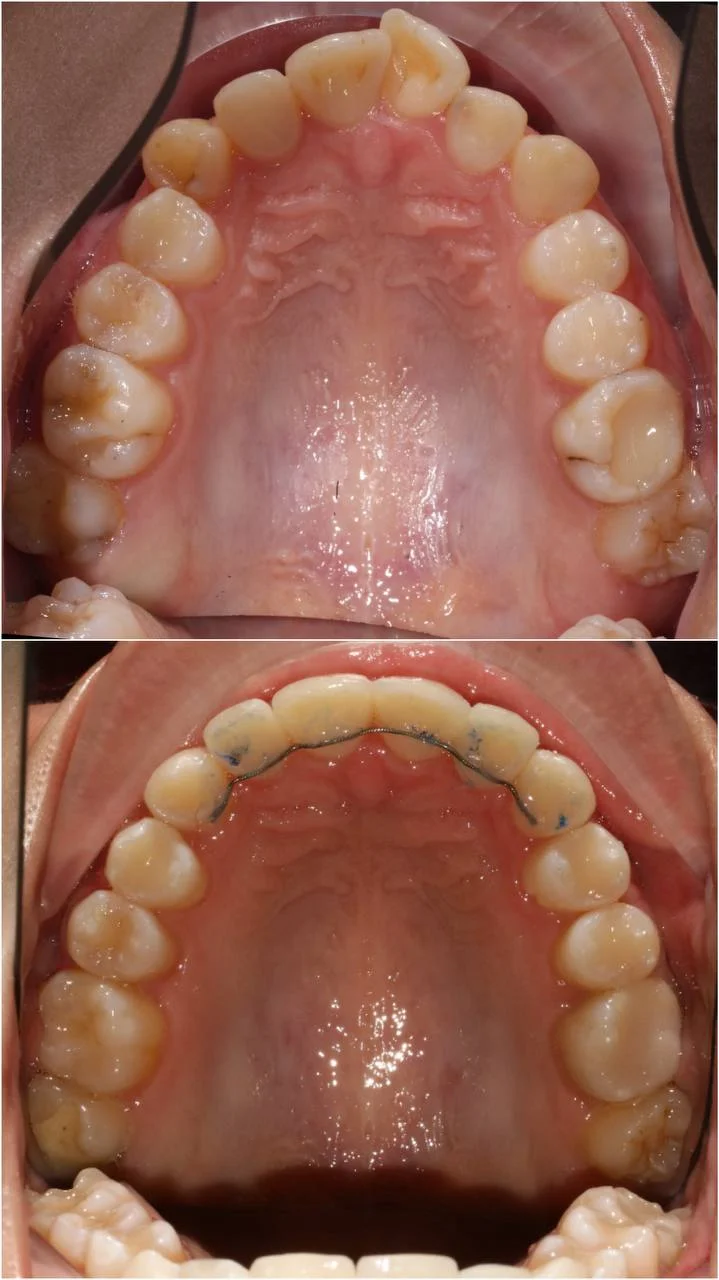

Проблема: В клинику обратилась пациентка — беспокоили неровные зубы и неправильное смыкание. Зубные ряды сходились некорректно, зубы стояли со смещением, что влияло и на внешний вид, и на распределение нагрузки при жевании.

Решение: Поставили элайнеры 3D Smile на обе челюсти. Лечение заняло 4 года и потребовало нескольких последовательных этапов коррекции. Капы менялись каждые 1–2 недели, на контрольных визитах отслеживали прогресс и выдавали новые наборы. Зубы встали в правильное положение, смыкание нормализовалось. Зафиксировали ретейнеры на обе челюсти, изготовили ретенционные капы. Пациентка прошла онлайн-консультацию с ортопедом для оценки дальнейших шагов.

Лечение потребовало нескольких последовательных этапов — каждый дозаказ кап уточнял положение зубов, которые не полностью отреагировали на предыдущий курс. Элайнеры 3D Smile позволяют работать поэтапно, корректируя план по ходу. Результат получен, ретейнеры зафиксированы. Рекомендовала пациентке консультацию ортопеда для оценки состояния зубов после лечения